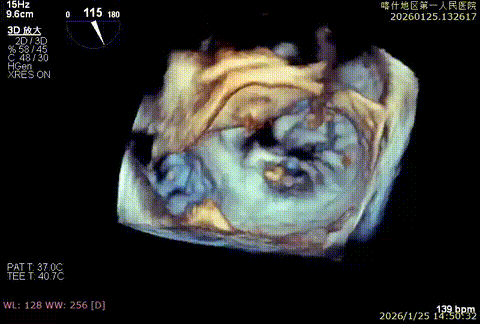

该例患者为DMR,脱垂区域较宽,术前制定手术策略:使用2把XTR先于患者外侧交界至1区部位进行钳夹。术中房间隔穿刺高度为4.0cm。成功穿刺后将SGC和XTR-CDS依次送入左心房,通过操控“M”旋钮调节SGC,使二尖瓣夹避开华法林脊,成功定位于2区正上方。在2区进行弹道测试成功后,进行Orientation调整。第一把于外侧交界区夹持,第二把于1区夹持,术中成功捕捞和夹持瓣叶后缓慢关紧夹臂,TEE检查见二尖瓣反流程度降低至1+,术后平均跨瓣压差3mmHg,手术顺利结束。

重度反流

3D enface进行Orientation调整